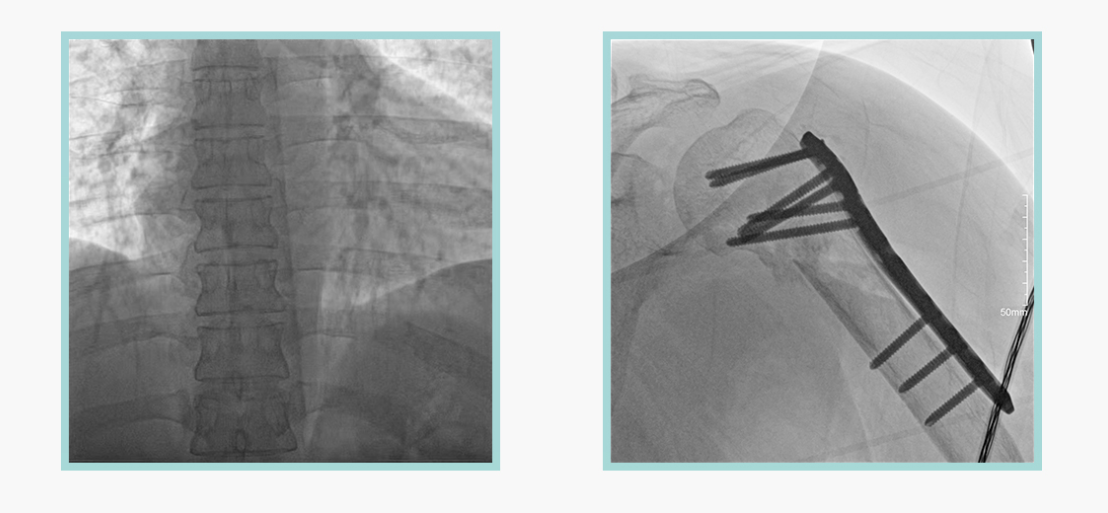

作为全球X线机的主要参与者,亿万28入口网页版-亿万28网页在线玩-万28官网下载最新版-亿万e网址pg-亿万28pg电子-亿万28赏金女王-亿万28娱乐科技在数字化X线产品线实现全线动态化之外,在移动C臂X光机产品线领域推出全新平板移动C臂产品:悦画。随着国家“千县工程”提升基层医疗卫生服务能力,外科对于手术介入引导设备的需求剧增。对于一台优秀的移动C臂X线机而言,如何保证最优质影像的同时,最大程度降低X线的辐射剂量,并在满足临床手术引导/定位的同时,最大程度的保护临床手术的医务人员,是悦画最为关切的问题。

亿万28入口网页版-亿万28网页在线玩-万28官网下载最新版-亿万e网址pg-亿万28pg电子-亿万28赏金女王-亿万28娱乐科技悦画移动C臂X线摄影系统,采用了业内技术最尖端的CMOS探测器。基于性能优异的针状CSI闪烁体涂层和高灵敏度的CMOS感光芯片,悦画可以实现在超低X线剂量条件下实现高清晰影像成像,相较于一般的影增移动C臂和平板C臂,动态范围更高,影像的层次感和对比度更好。

在产品的性能参数设计上,悦画的像素可达到200万,空间分辨率可达到3.2线对,采用16bit的影像灰度,悦画在影像后处理上,通过SPI金字塔图像算法,支持摄影、脉冲透视影像、连续透视等多种模式下的影像采集,动态透视影像视频支持保存与回放。双大屏的设计,透视影像支持三档放大,保证临床影像读取的便利。

此外,骨科手术时间平均时长约为45分钟左右时间,长期的X线透视或摄影曝光剂量将对临床手术与操作医务工作者造成难以评估的健康风险,悦画通过支持摄影曝光参数的自主调节,可以保证在最低剂量水平下输出满足临床手术定位与引导所需要的影像质量,相较于市面上的固定曝光参数配置移动C臂,自主参数调节设计的曝光功能设计,可以大幅减少医务工作者的X线辐射剂量。

悦画在影像的伪影处理上,也积累多项图像处理专利技术。通过对植入物的精准识别,悦画能够精准祛除植入物伪影与运动伪影,保证高质量的影像输出,无论是影像的对比度、分辨率(清晰度)相较于市面上的移动C臂产品都更胜一筹。